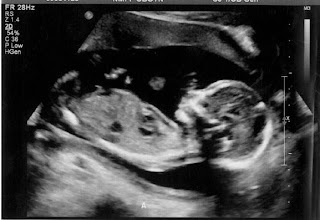

A baby update! We're in full swing with our doctor visits every two weeks now. My mom came with me this week while E was out of town for work, and what a fun day it was to share with her. I'm always nervous as we lay back and wait to see what comes up on the screen, but I'm getting more comfortable each time and always looking forward to seeing how much bigger they are and how much they're moving around.

Baby A above, Baby B below - go figure, identical in size :) And amniotic levels were ideal! We're entering into a critical time where we're watching close for signs of Twin to Twin Transfusion Syndrome, where one twin is getting more blood and/or nutrients than the other, and so far we're in the clear. I couldn't be more thankful. I'm even thankful for the 16lbs I've put on and the fact it all seems to be in the form of belly and boob growth and not hips, thighs, face... yet.

The babies are both measuring about a week ahead actually, I'll take it! And if you've come this far, I can't believe I get to protect and love these two little GIRLS! Josie's coming around to the idea that she's going to be a big sister, and I have no doubt she'll have these girls thinking that she's the boss on day one. I can't wait for my house of girls!